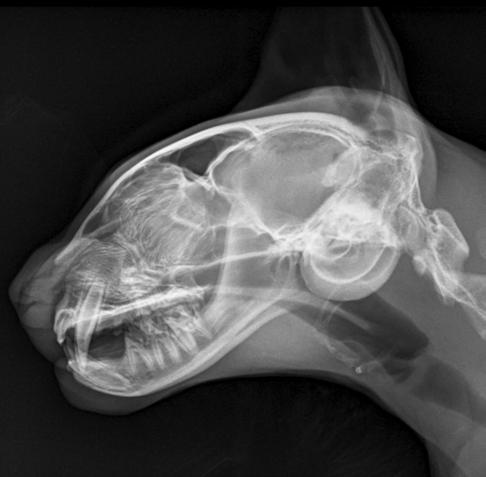

1. Radiografías de la cabeza de un gato maine coon de un año de edad. (A) Proyección lateral. (B) Proyección dorsoventral. (C) Rostro 10º ventrodorsocaudal oblicua.

En la exploración otológica se visualizó una masa en el conducto auditivo externo izquierdo, apreciable desde la abertura del pabellón auricular. La masa era sólida, poco móvil y obstruía totalmente el canal auditivo. El resto del examen físico y pruebas de enfermedades víricas fueron normales. En el análisis sanguíneo se evidenció neutrofilia con desviación a la izquierda y trombocitosis.